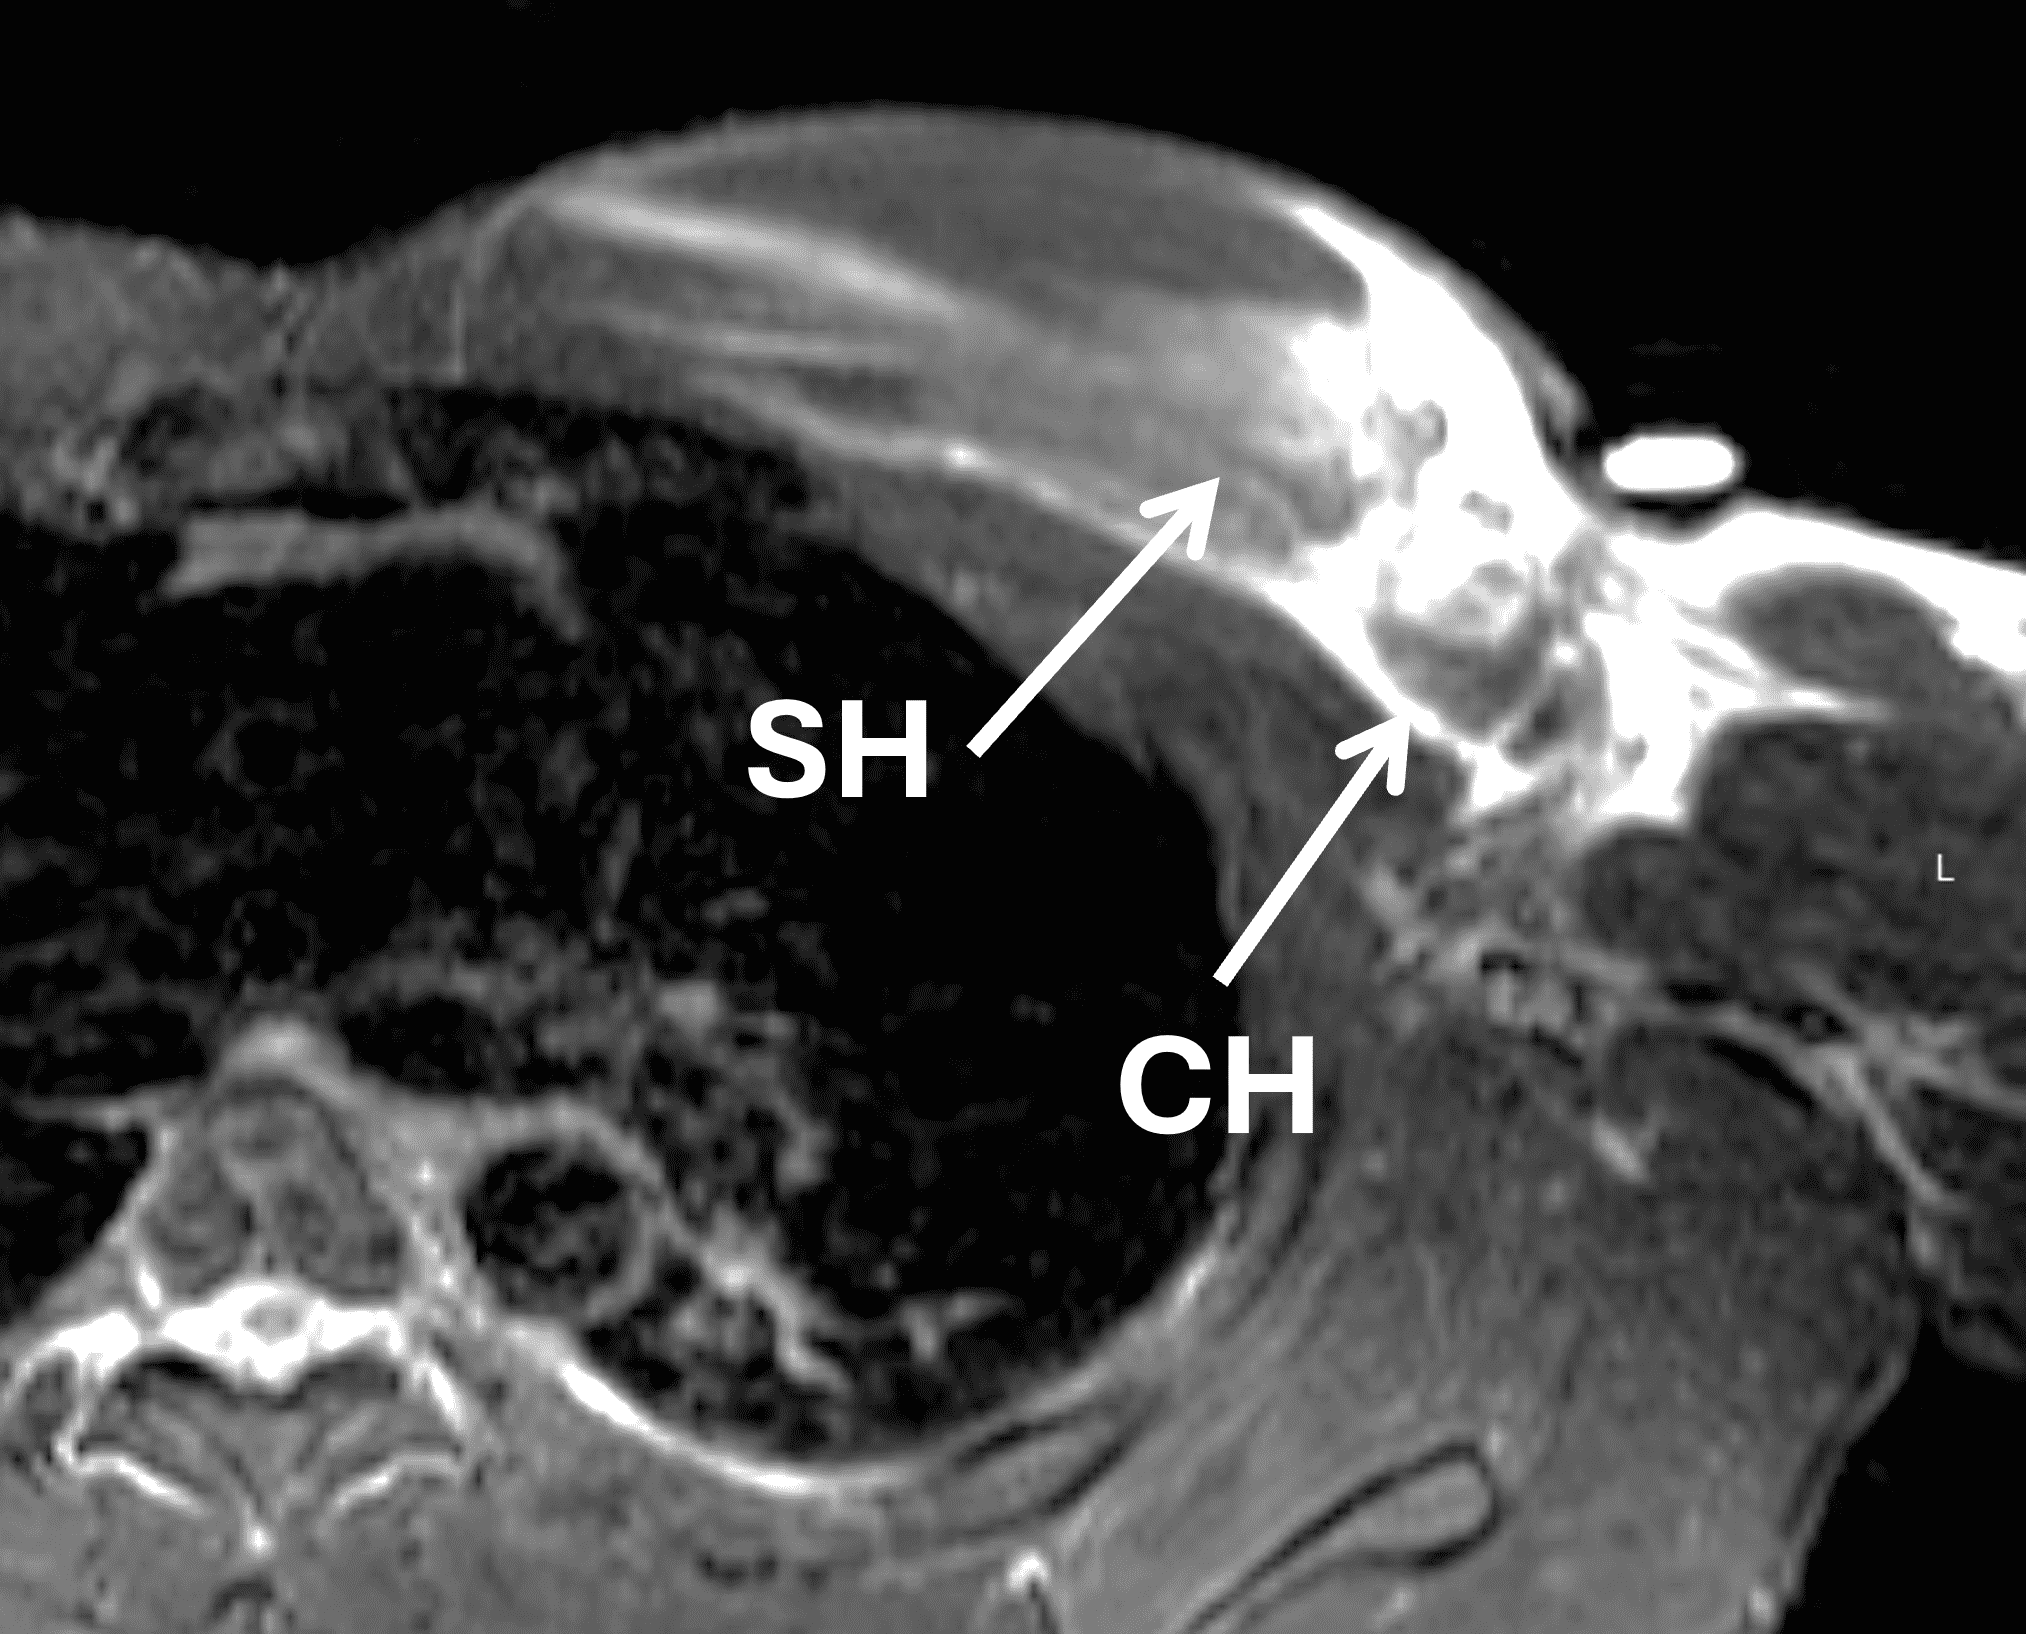

The PM is a large, fan-shaped, multipennate muscle composed of clavicular, sternocostal and abdominal heads (Figure 3). The muscle has a broad origin from the clavicle, sternum, costal cartilages 1-6 and aponeurosis of the external oblique muscle.4 The sternocostal head (SH) is composed of 7 segments and analogous to an unfolded, articulated hand fan, with the superior muscle segments lying anterior to the more inferior segments (Figure 5).5 The deltopectoral groove, containing the cephalic vein, marks the border between the anterior deltoid muscle and the clavicular head (CH) of the pectoralis muscle, and is an important landmark during surgical exploration. A rare accessory head called the chondrocoracoideus muscle originates from the PM lateral border, runs deep to the PM tendon humeral insertion and joins the short of biceps tendon at the coracoid process, and is potentially a source of neurogenic thoracic outlet syndrome.6 Additional rare but recognized local muscle anomalies include unilateral congenital absence or hypoplasia of the PM major muscle (typically as a part of Poland syndrome), the sternalis muscle and the chondroepitochlearis muscle.7 The pectoralis minor muscle runs deep to the PM, originating from the ribs and inserting on the medial margin of the coracoid process.7 The SH seventh sternal segment is equated to the abdominal head by some authors.8 The CH is a single segment arising from the anterior margin of the medial clavicle. Cadaveric studies report a mean muscle fiber length of 15.0 cm +/- 0.8 cm for the CH, and 16.4 cm +/- 1.2 cm for the SH.3 The difference in muscle fiber length and pennation angle may influence the location of injury during specific activities or injury mechanisms.9,10

Figure 13: Complete (2-layer) pectoralis major tear at the myotendinous junction. (13A) Coronal STIR image shows complete fiber disruption at the myotendinous junction (arrows) in the medial lip of the axilla. (13B) Axial fat-suppressed T2-weighted image confirms involvement of both the sternal head (SH) and clavicular head (CH). (13C) Axial T1-weighted image shows the intact tendon insertion on the humerus (arrows).